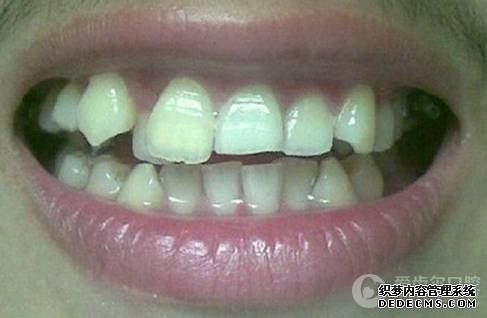

临床诊断:通过3D数字化全景机的拍片检查,患者上下牙排列拥挤,前牙受挤压向内歪斜,咬合关系异常,唇形尚可,颞下颌关节检查未见异常,无蛀牙、牙周疾病症状。经过和患者商量,选定自锁托槽矫正方案,调整牙间隙,恢复牙齿的正常排列,实现正常的咬合关系。

矫正前照片